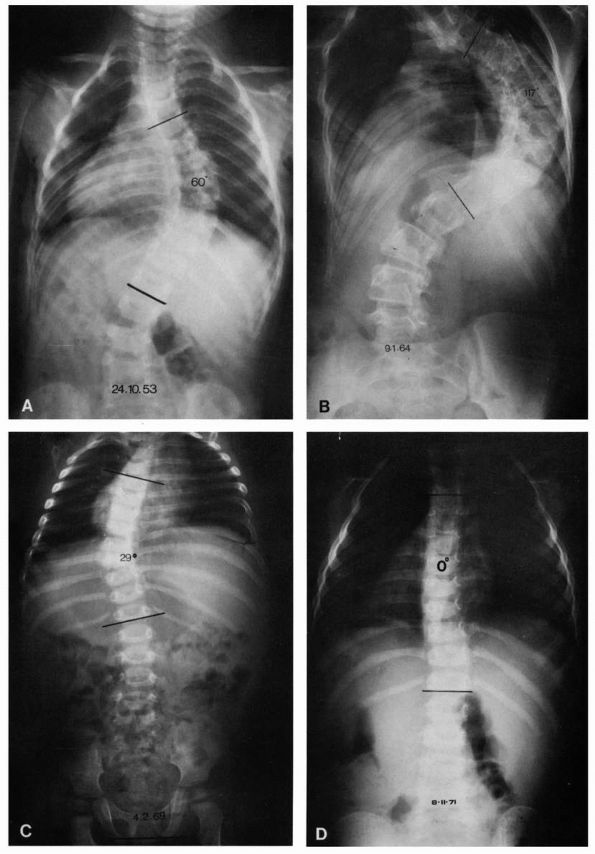

![]() |

FIGURE 16-8. (A) Progressive type of infantile idiopathic scoliosis, early radiograph. Curve measures 60°. (B) Late radiograph showing marked increase of primary curve and developing secondary curves. (C) Resolving type, early radiograph. Curve measures 29°. No secondary curve. (D) Resolving type, later radiograph. Curve reduced to zero. (Courtesy of Dr. J. I. P. James)